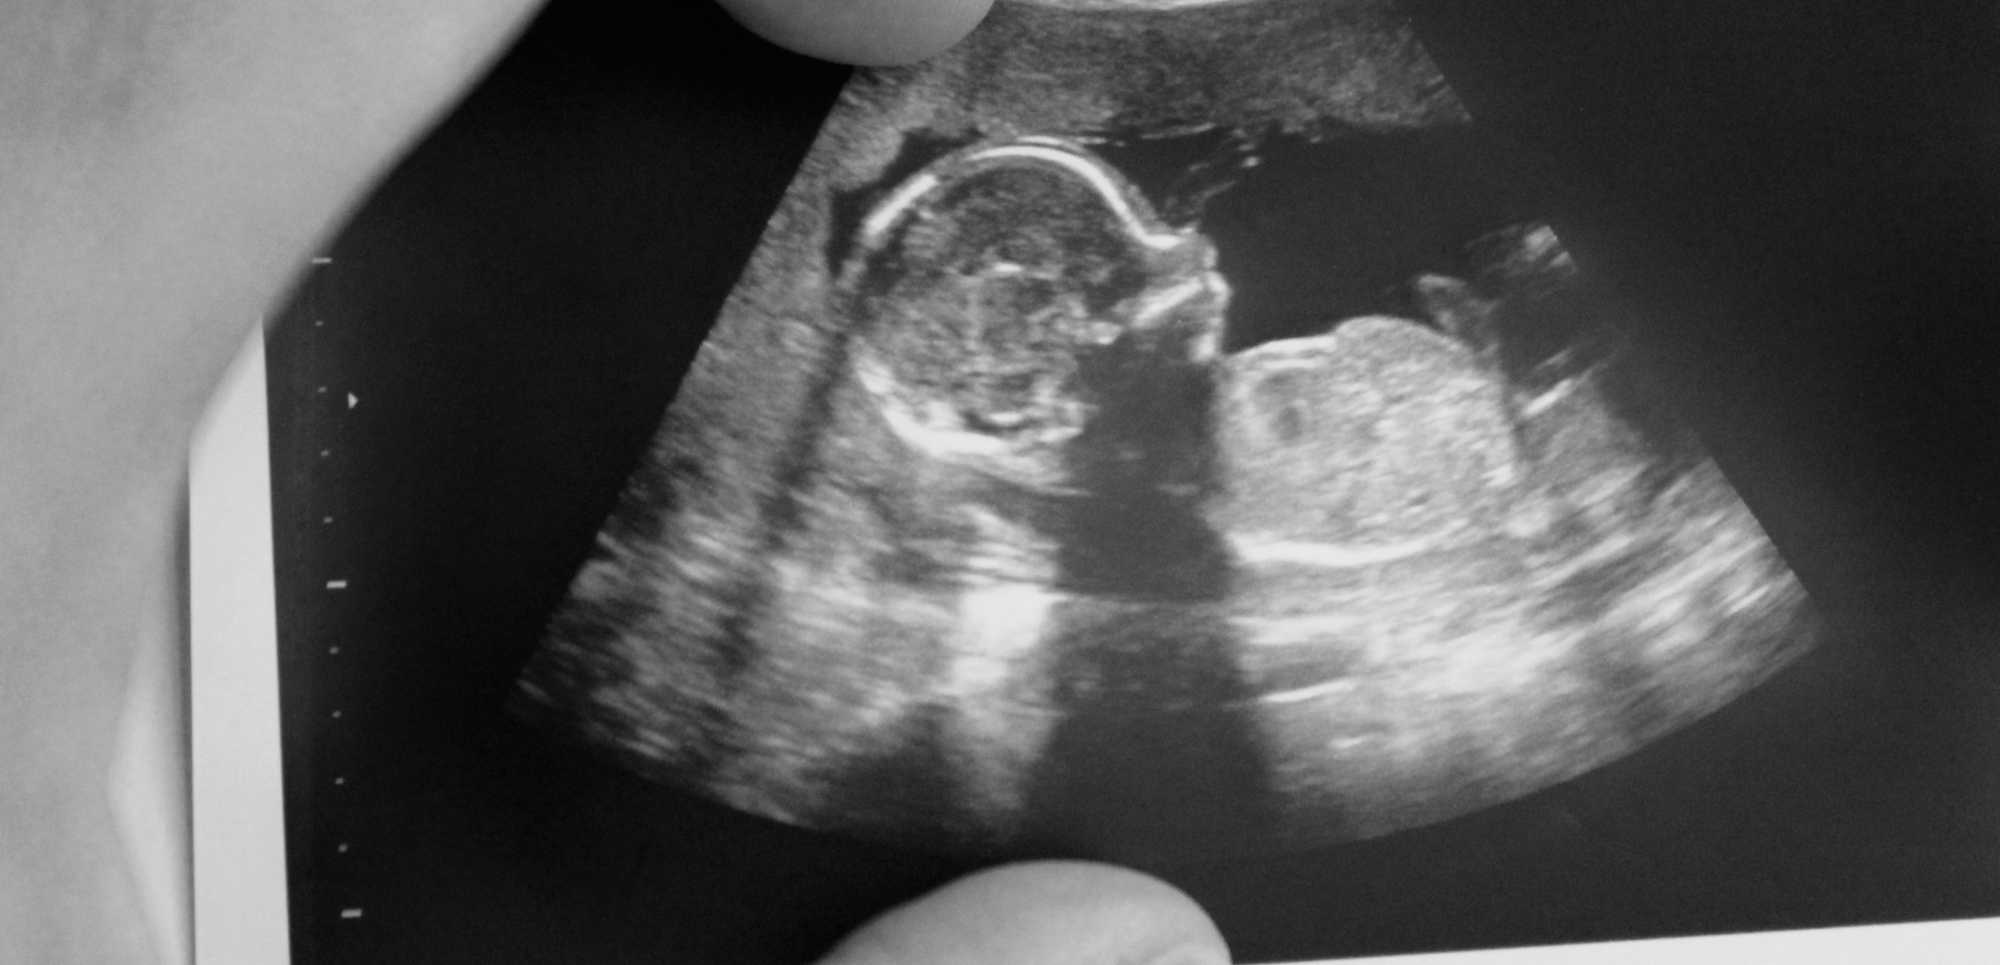

O primeiro ultrassom na gravidez é um momento especial e essencial para garantir um acompanhamento adequado da gestação. Ele permite confirmar a gestação, avaliar a saúde do bebê e identificar possíveis condições que necessitem de atenção médica precoce.

Geralmente, o primeiro ultrassom é realizado entre a 6ª e a 8ª semana de gestação. Nessa fase inicial, o exame já pode detectar o saco gestacional e, muitas vezes, o batimento cardíaco do embrião. Esse exame é fundamental para confirmar a viabilidade da gestação e estimar a idade gestacional, ajudando a definir a data provável do parto.

Durante o primeiro ultrassom, o médico avalia:

- Presença do saco gestacional e embrião;

- Frequência cardíaca fetal;

- Localização do embrião (para descartar gestação ectópica);

- Número de fetos, confirmando se é uma gestação única ou múltipla;

- Estruturas iniciais do útero e ovários da mãe.